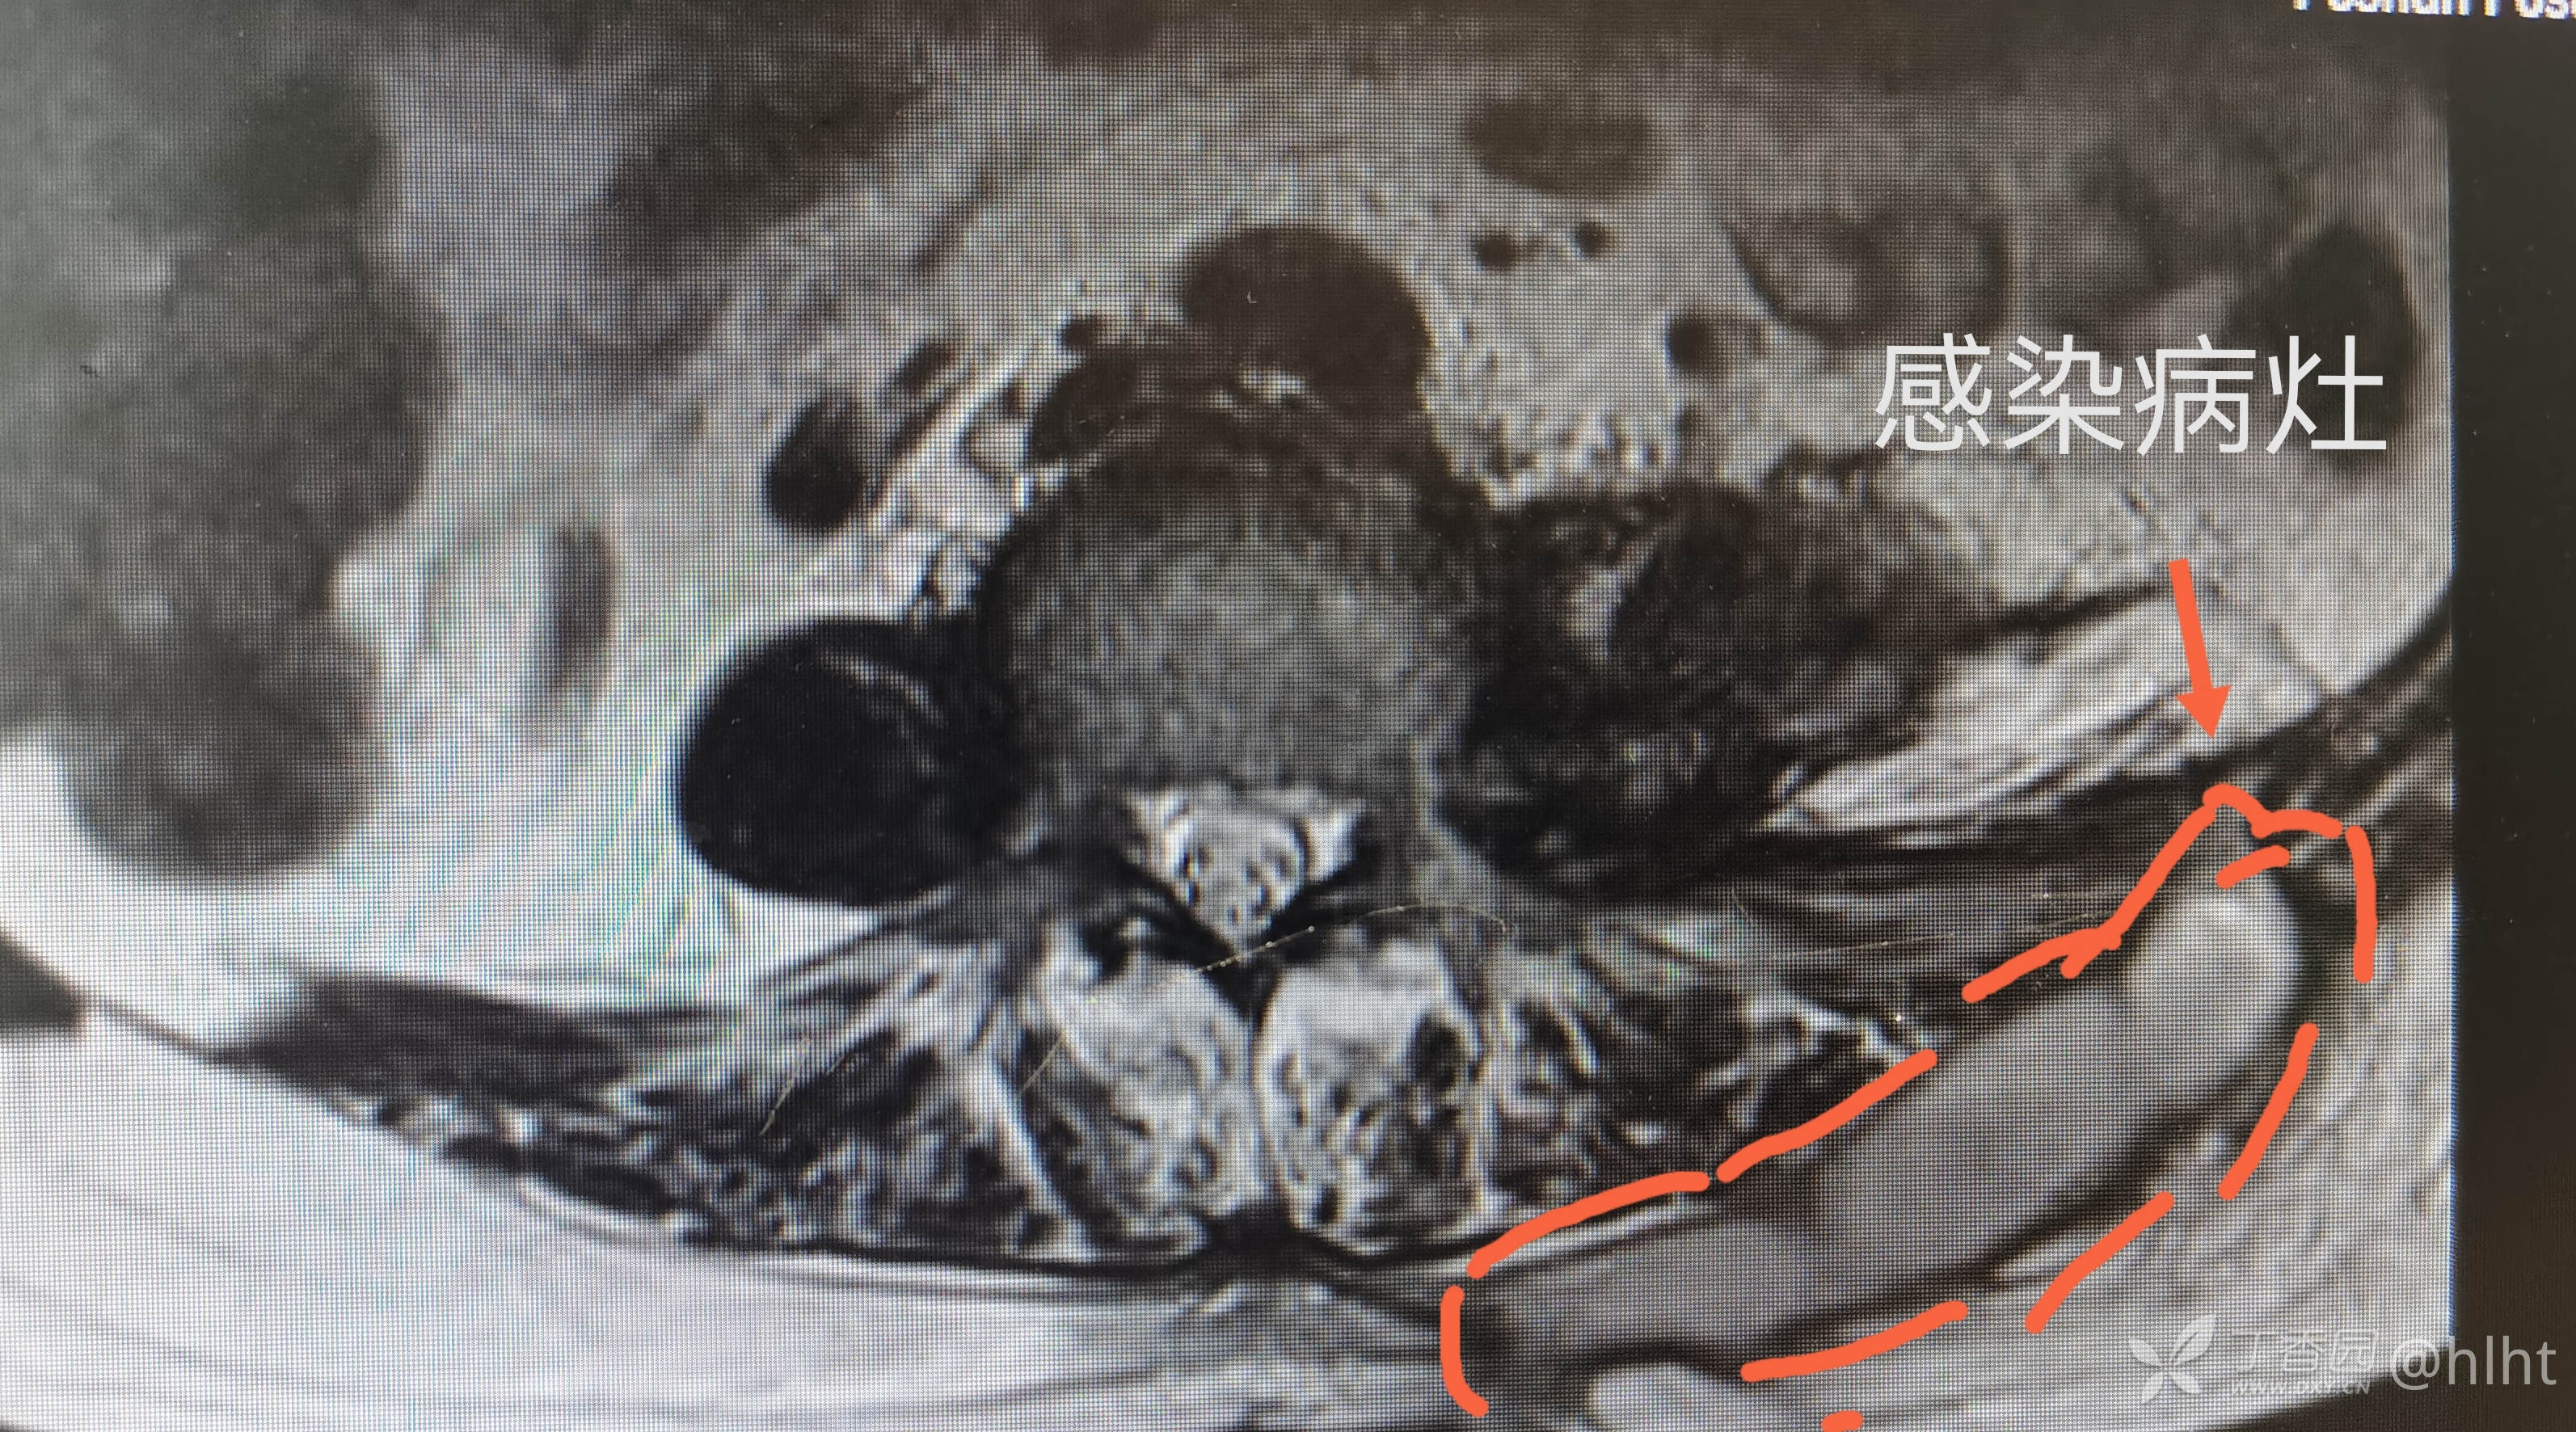

诊断:1.左侧腰大肌、髂腰肌脓肿 :结核? 2.2型糖尿病 3.高血压2级